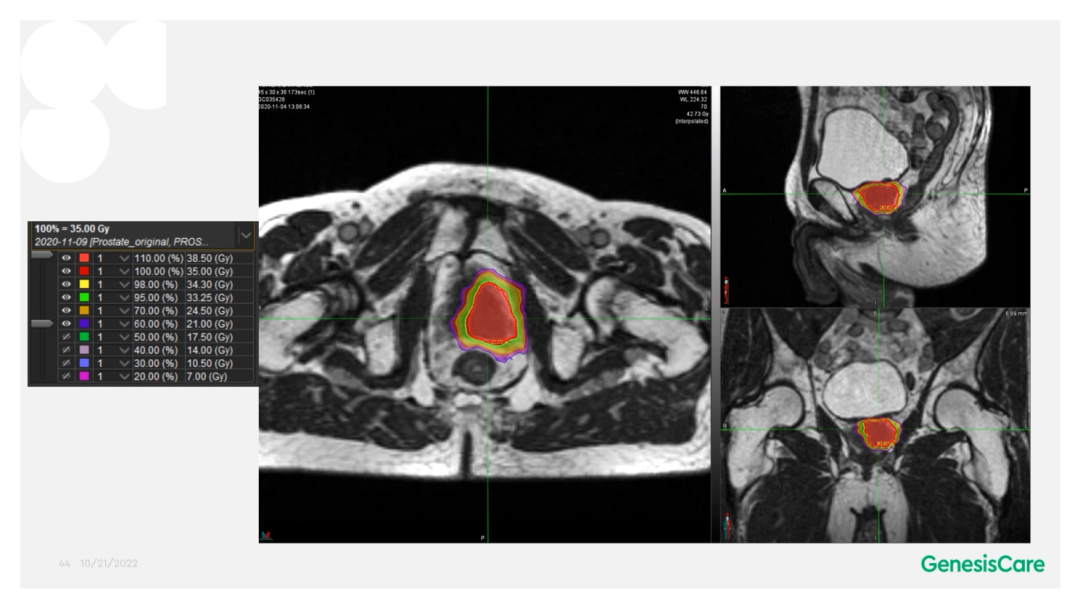

Dr. Camilleri表示,他们在做在线自适应放疗的时候,为了提高速度,仅对靶区外放3cm以内的危及器官的变化进行自适应调整或重新勾画轮廓,见Figure 13。这样可以缩短轮廓勾画的时间。对于放疗计划,使得95%的靶区体积接受到100%的处方剂量覆盖,并将最大剂量限制为2%的靶区体积不超过处方剂量的110%,这样就能保证在图像上很难显示的尿道不会超量,见Figure 14。另外,在制作放疗计划时,将PTV分为PTV LOW和PTV High,PTV和危及器官重叠的部分为PTV LOW,将PTV LOW的剂量目标设定在危及器官的耐受剂量以下,这样就能保证危及器官不超量,见Figure 15。